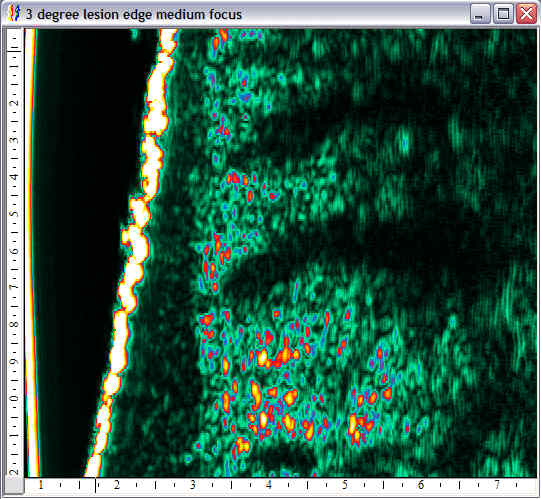

| Pressure wounds |  Pressure wound, edge |

Pressure wound, open |